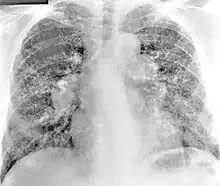

Definitive diagnosis of berylliosis is based on history of beryllium exposures, documented beryllium sensitivity and granulomatous inflammation on lung biopsy. Given the invasive nature of a lung biopsy, diagnosis can also be based on clinical history consistent with berylliosis, abnormal chest x-ray or CT scan findings, and abnormalities in pulmonary function tests.[16]

Chest radiography findings of berylliosis are non-specific. Early in the disease radiography findings are usually normal. In later stages interstitial fibrosis, pleural irregularities, hilar lymphadenopathy and ground-glass opacities have been reported.[18][19] Findings on CT are also not specific to berylliosis. Findings that are common in CT scans of people with berylliosis include parenchymal nodules in early stages. One study found that ground-glass opacities were more commonly seen on CT scan in berylliosis than in sarcoidosis. In later stages hilar lymphadenopathy, interstitial pulmonary fibrosis and pleural thickening.[19]